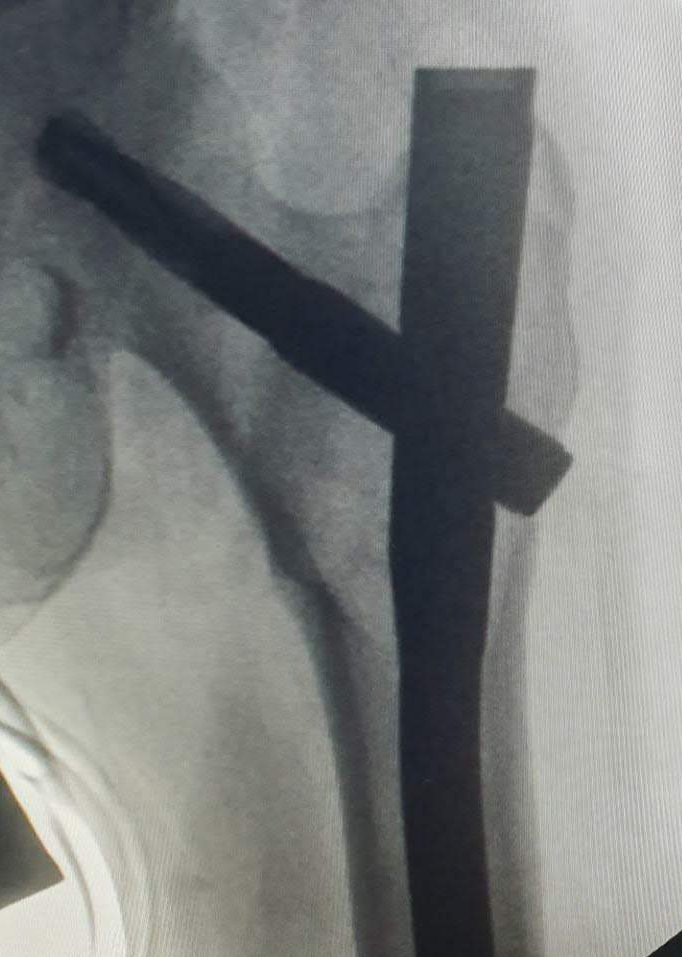

PROFILE TRAINING AND PRESENTATION Dr. Niranjanan Recieving Diploma SICOT degree in Rome, Italy Dr. Niranjanan being awarded fellowship certificate at Indian spinal injuries centre CLIINIC SOME OF Dr. NIRANJANAN's CASES